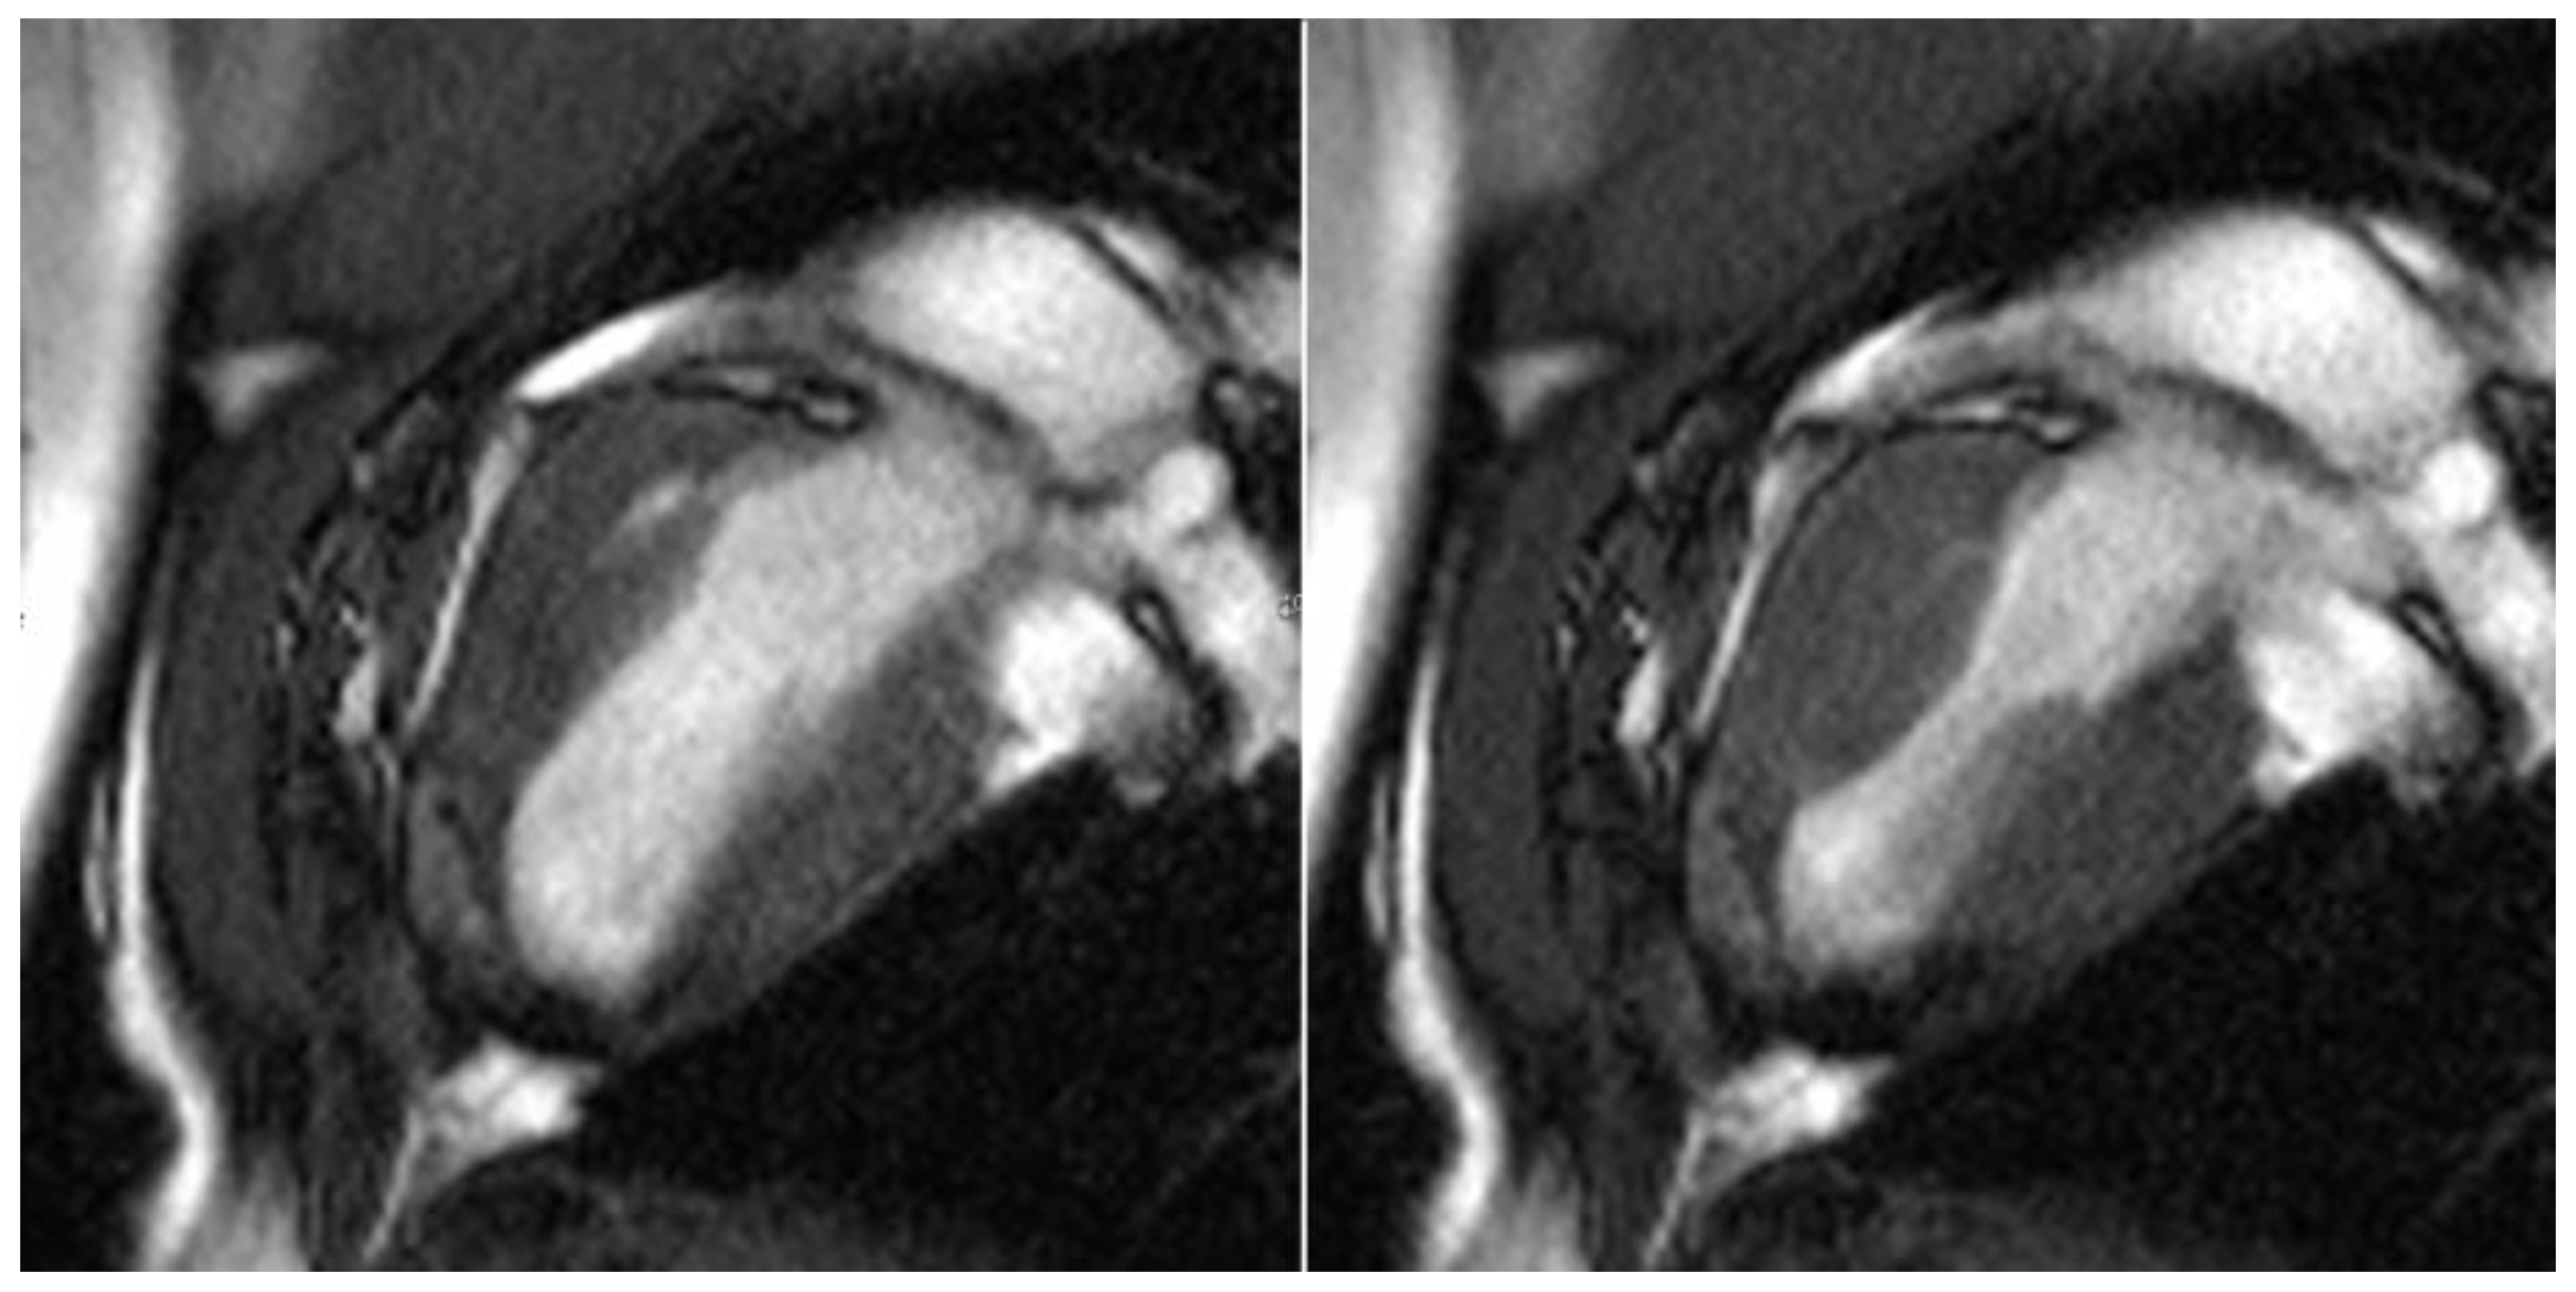

All test animals were examined six months after successful surgery using cardiac MRI to evaluate the morphology and function of the left ventricle, particularly in the area of the transplanted patches of stomach tissue. In line with the macroscopic findings, stable integration of the stomach patch through adjacent cicatricial tissue could be detected in animals without an aneurysm (see Figure 7).

Figure 7.

Cardio MRI six months following myocardial reconstruction with a vascularized stomach patch, stabilized with degradable magnesium alloy scaffolds. Cine SSFP in left ventricular two-chamber view. Left: end-diastolic phase, right: end-systolic phase. Good integration of the transplanted stomach patch.